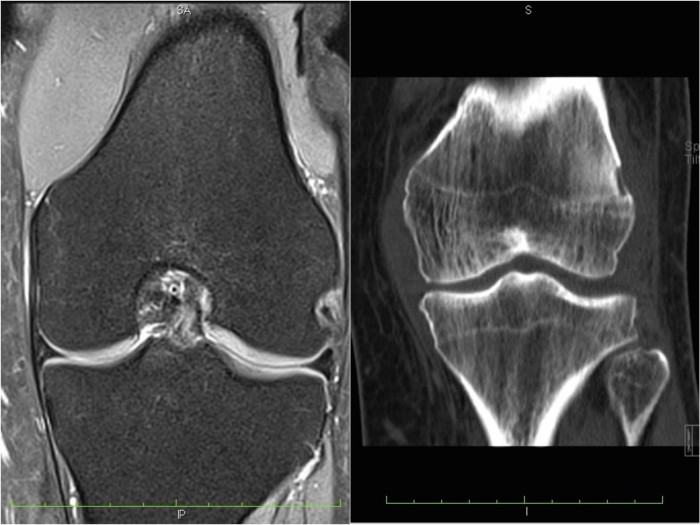

Różnica pomiędzy badaniami rezonansem magnetycznym (po lewej), a tomografią komputerową (po prawej). MRI dużo lepiej obrazuje tkanki miękkie, w TK ocenie poddawane są głównie elementy kostne.